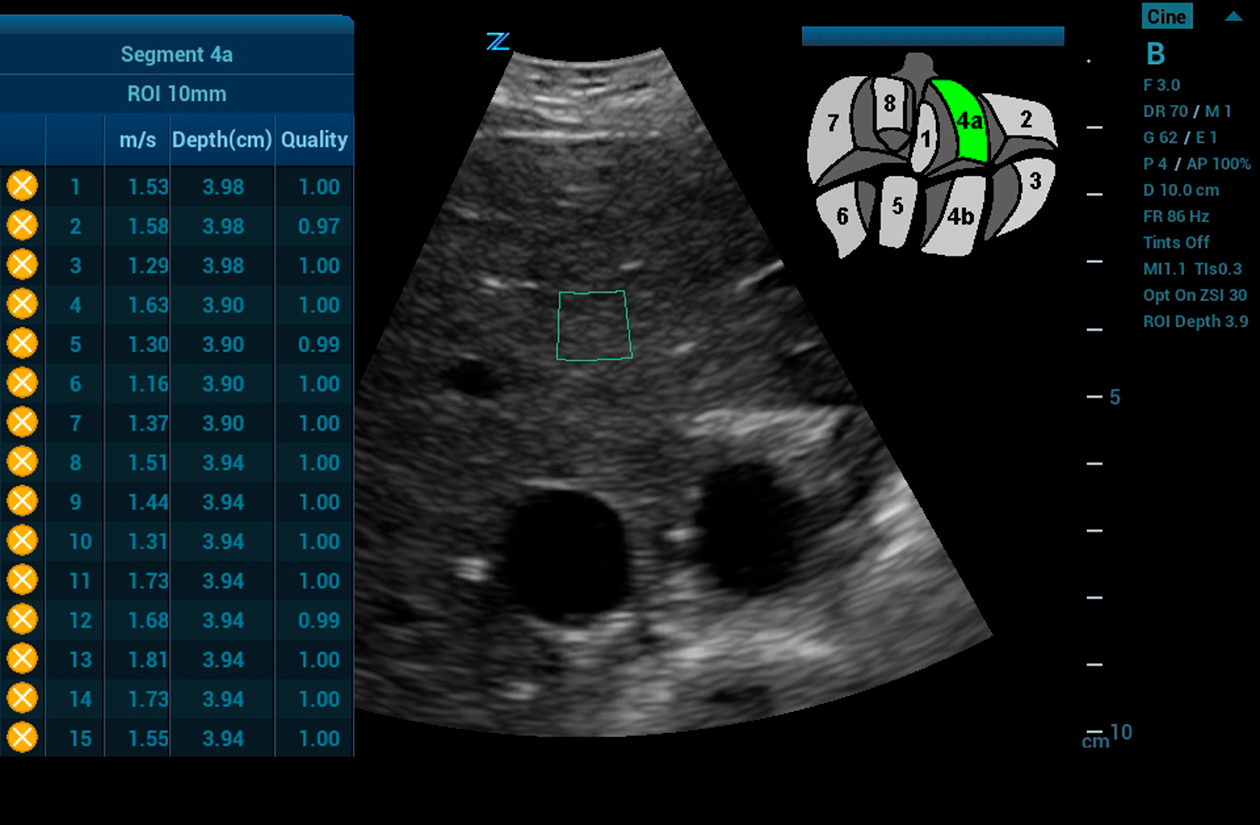

ARFI

ARFI Elastography* with quantification is a non-invasive method of assessing liver tissue stiffness. Using real time imaging as a guide, ARFI automatically calculates liver tissue stiffness values (AVG, MEAN, and IQR) for a predetermined region of interest. Multiple samples can be recorded and displayed in a report.

* Available on the C4-1 transducer